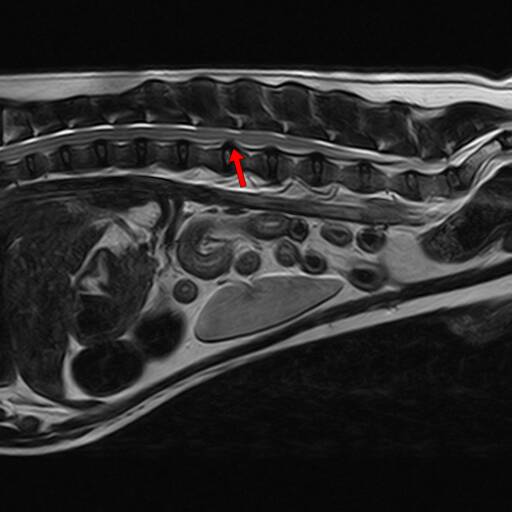

椎间盘突出(图一) 椎间盘突出(图二)